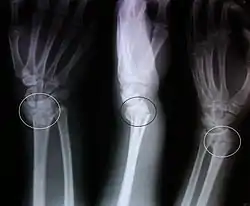

La fractura de Colles es una fractura distal del radio. La fractura se reconoce clínicamente por la deformidad en "dorso de tenedor" debido al desplazamiento dorsal del fragmento distal del radio. Para una discusión más detallada, ver la fractura distal del radio.

![]() Imagen radiográfica anteroposterior y lateromedial de una fractura de Colles | ||

Hallazgos radiológicos típicos

- Inclinación dorsal y radial de la muñeca.

- Acortamiento radial.

- Desplazamiento dorsal del fragmento distal.

- A menudo asociada a fractura del apófisis estiloide cubital.

- Ángulo volar < 10°.